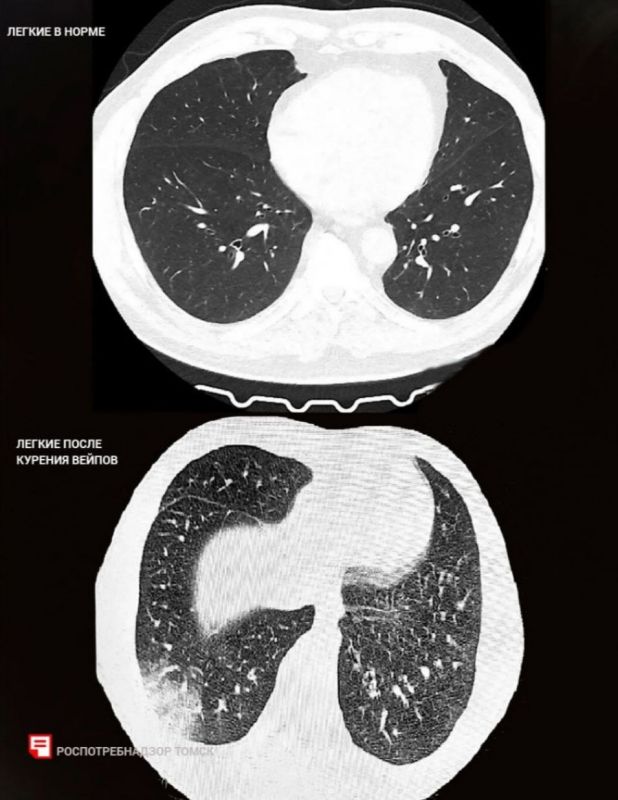

Её называют «попкорновой».Переборщили с вейпом двое подростков из Томска. Теперь у них лёгкие звучат, как лопающийся попкорн (отсюда и название). А ещё воспаление и повреждение дыхательных путей.Чёткого метода, как лечить эту болезнь, пока...